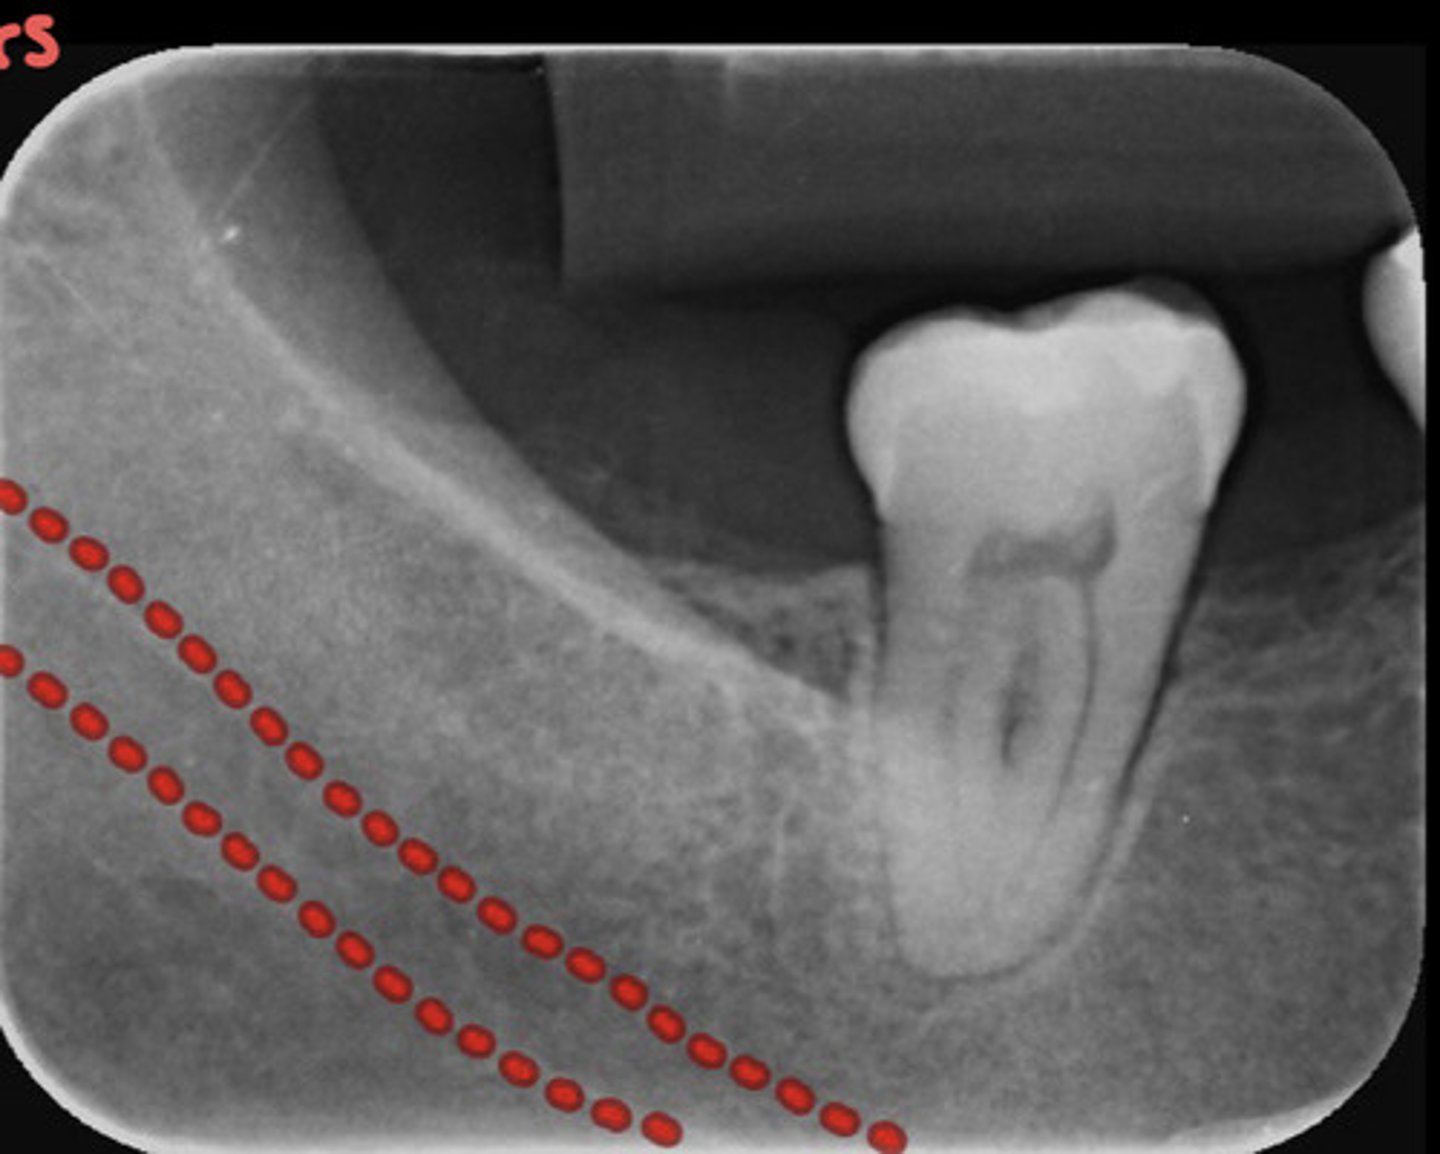

What does the mandibular canal look like radiographically?

information on mandibular canal

radioluncentt band, with two thin radiopaque line & below the apices of the mandibular molar teeth

1. external oblique

2. Inferior oblique (mylohyoid ridge)

3. mandibular canal

4. mandibular gland fossa

5. inferior border of mandible

information on mylohyoid ridge

dense radiopaque band that extends downward and forward from the third molar region at the level of the apices of the posterior teeth

appears as a radiopaque band extending downward and forward from the anterior border of the ramus of the mandible

-starts behind last tooth and comes forward